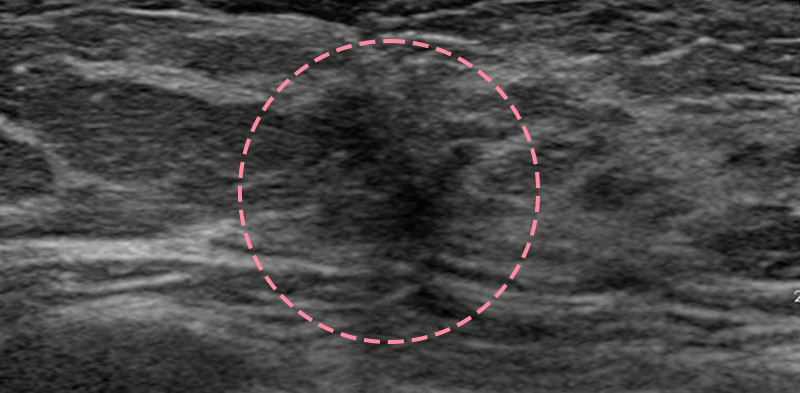

유방 양성 종양은 한 개만 나타나는 것이 아니라 동시다발적으로 생겨나기도 합니다.

여러 개의 양성 종양 제거는 정상적인 유방 조직을 온전히 보전할 수 있도록 섬세한 시술이 필요합니다.

한송이 원장은 다발성 종양 제거에 대한 풍부한 경험을 토대로, 무리 없이 맘모톰 조직검사 및 제거를 진행했습니다.

맘모톰시술 6개월 후 유방초음파 검사 시행 결과 종양이 깨끗하게 제거됨을 확인했으며, 약간의 반흔 조직이 남았으나 시간이 지나면서 대부분 사라지기 때문에 좋은 예후가 기대되었습니다.